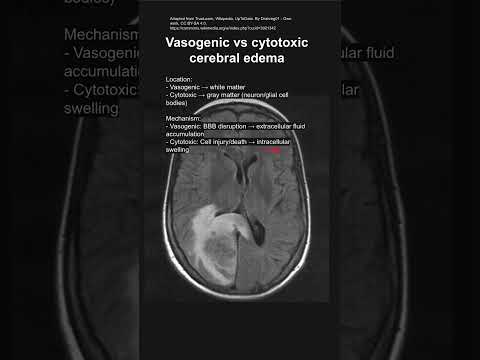

Vasogenic edema, huh? Sounds all fancy, right? But really, it’s just a term that describes a kind of swelling in the brain. Basically, when there’s an injury or some kind of trauma, the blood-brain barrier gets a little messy. This allows fluid to leak into the surrounding tissue, leading to that swelling. That’s what vasogenic edema is all about.

So, let’s chat about vasogenic edema, shall we? This is a fancy term for swelling in the brain that happens when fluid leaks into the spaces around brain cells. It’s often linked to things like tumors, infections, or injuries. Pretty serious stuff, right? A lot of times, doctors try to manage this condition with medications. But then you might wonder: what’s the **optimal drug** for treating this kind of edema?

Vasogenic edema is a condition where excess fluid builds up in the brain’s surrounding tissues. This can lead to pressure inside the skull, causing some pretty serious concerns. You might think this sounds complex, but let’s break it down in simple terms so you can get a good grasp of it.